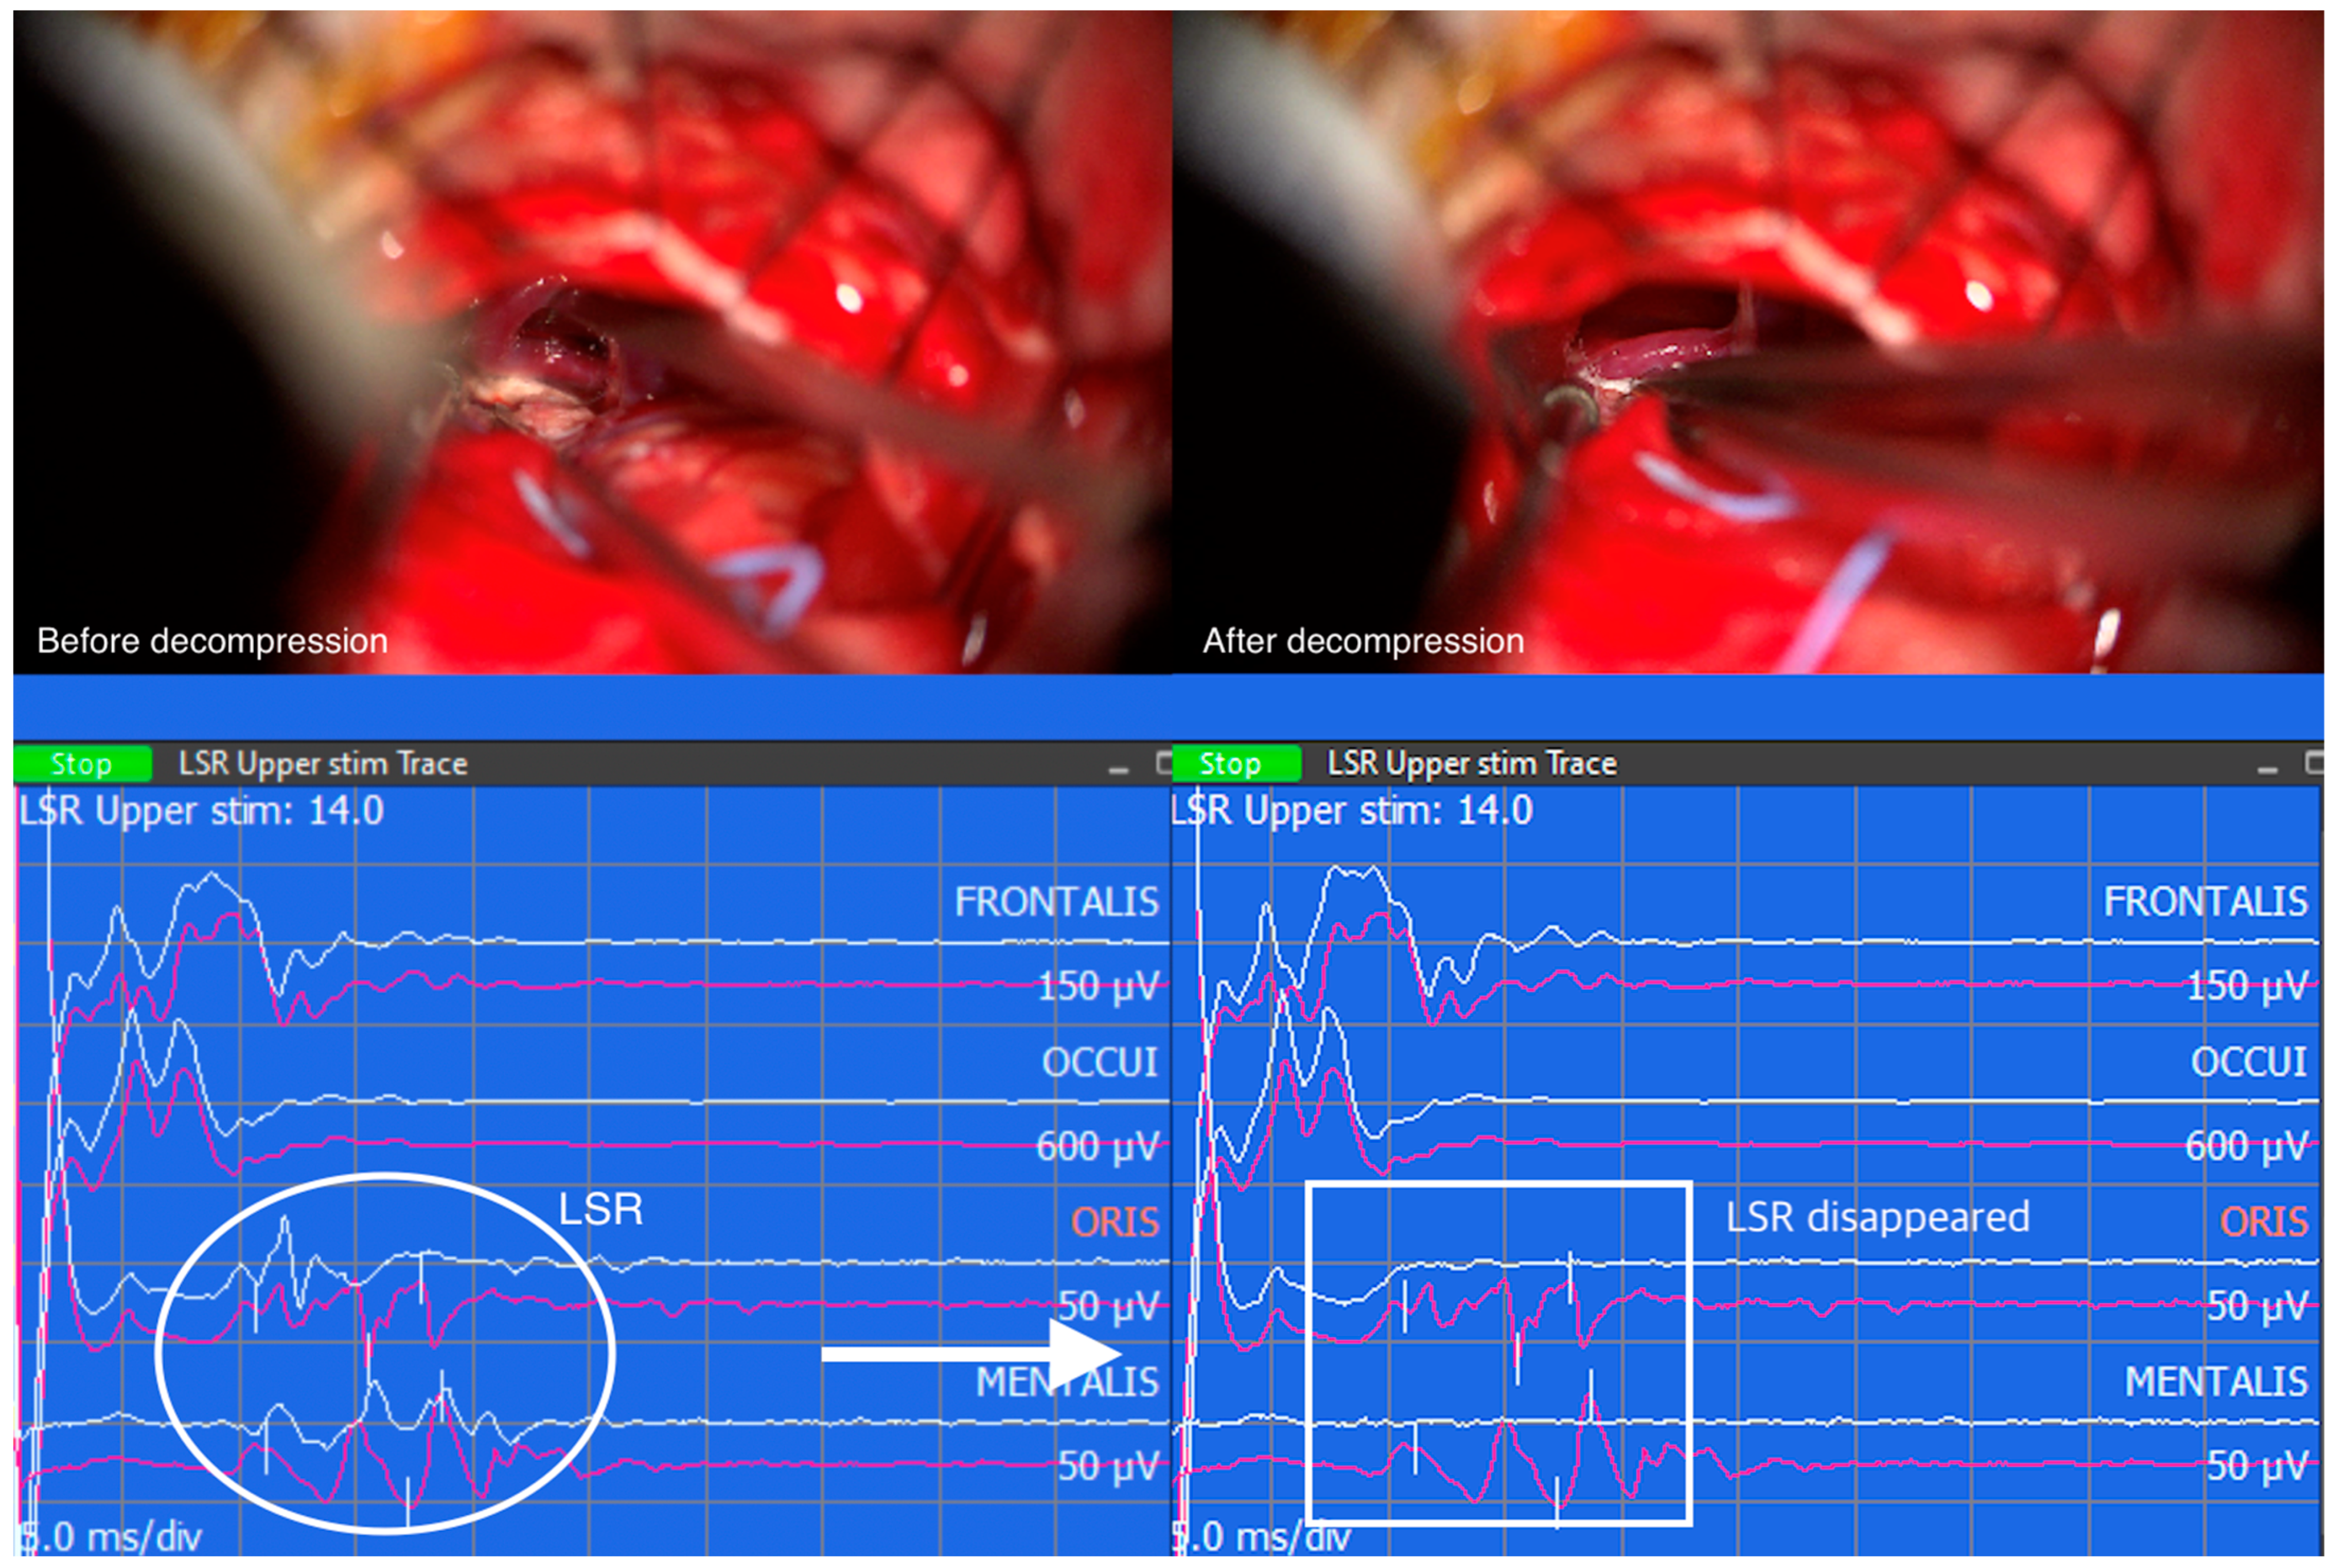

Similarly, when LSR persists despite successful decompression, the correlation between LSR and clinical outcomes becomes less straightforward. The persistence of LSR may indicate the presence of additional contributing factors or complexities that influence the overall outcome. These cases highlight the multifactorial nature of HFS and the need for a comprehensive assessment of various clinical factors to determine the prognosis and treatment outcomes accurately. However, the resolution of LSR followed by successful decompression of the vessel compressing the facial nerve REZ suggests a positive clinical outcome (Figure 3).

Figure 3. Captured image from intraoperative neuromonitoring program. The offending vessel was dissected from the facial nerve root exit zone, but teflon felt was not yet inserted. As a result, lateral spread response (LSR) is still seen (white oval). After placing teflon felt between the facial nerve and the dissected vessel, LSR disappeared (white rectangle).